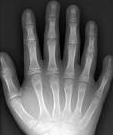

연골외배엽 이형성증(Chondroectodermal Dysplasia)은 짧은 사지, 다지증(손가락이나 발가락의 숫자가 정상보다 많음), 골격의 발육 부전, 손발톱과 치아의 발육 부전 등의 특징을 보이는 선천적 왜소증으로, 아주 드문 유전 질환입니다. 1940년에 엘리스-반-크레벨트 증후군(Ellis-van Creveld 증후군, EVC)으로 명명되었습니다. 발생 빈도는 많지 않고, 성별의 차이는 없습니다. 주로 미국 펜실베니아주 랭카스터 지방의 아미쉬 구교도에게서 발견되었습니다.

- 사지 : 불균등하고 짧은 사지(말단부가 더 심함), 다지증(특히 새끼손가락 옆에 손가락이 더 있음), 짧고 평평한 중지절, 지절 말단의 형성 부전(2~5번째 손가락 끝이 옥수수 형태임), 외반슬이 동반된 경골 상부 측면의 형성 부전, 만곡족

연골외배엽 이형성증은 특징적인 임상 증상으로 진단할 수 있습니다. 방사선 촬영을 통해 사지, 흉곽, 골반의 기형을 확인할 수 있습니다. 또한 ECV와 ECV2 유전자에 대한 돌연변이 검사로 유전적 진단을 할 수 있습니다.